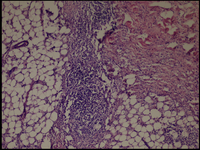

The histologic sections of [patient (a), taken by punch biopsy (4mm) from right thigh] revealed superficial and deep, intense plasma cellular and lymphocytic infiltrate, primarily in the lower dermis and fat septae with spillover to the fat lobules. Fibrosis was present in the deep dermis and in the fat. There was no vasculitis. (Fig 7,8).